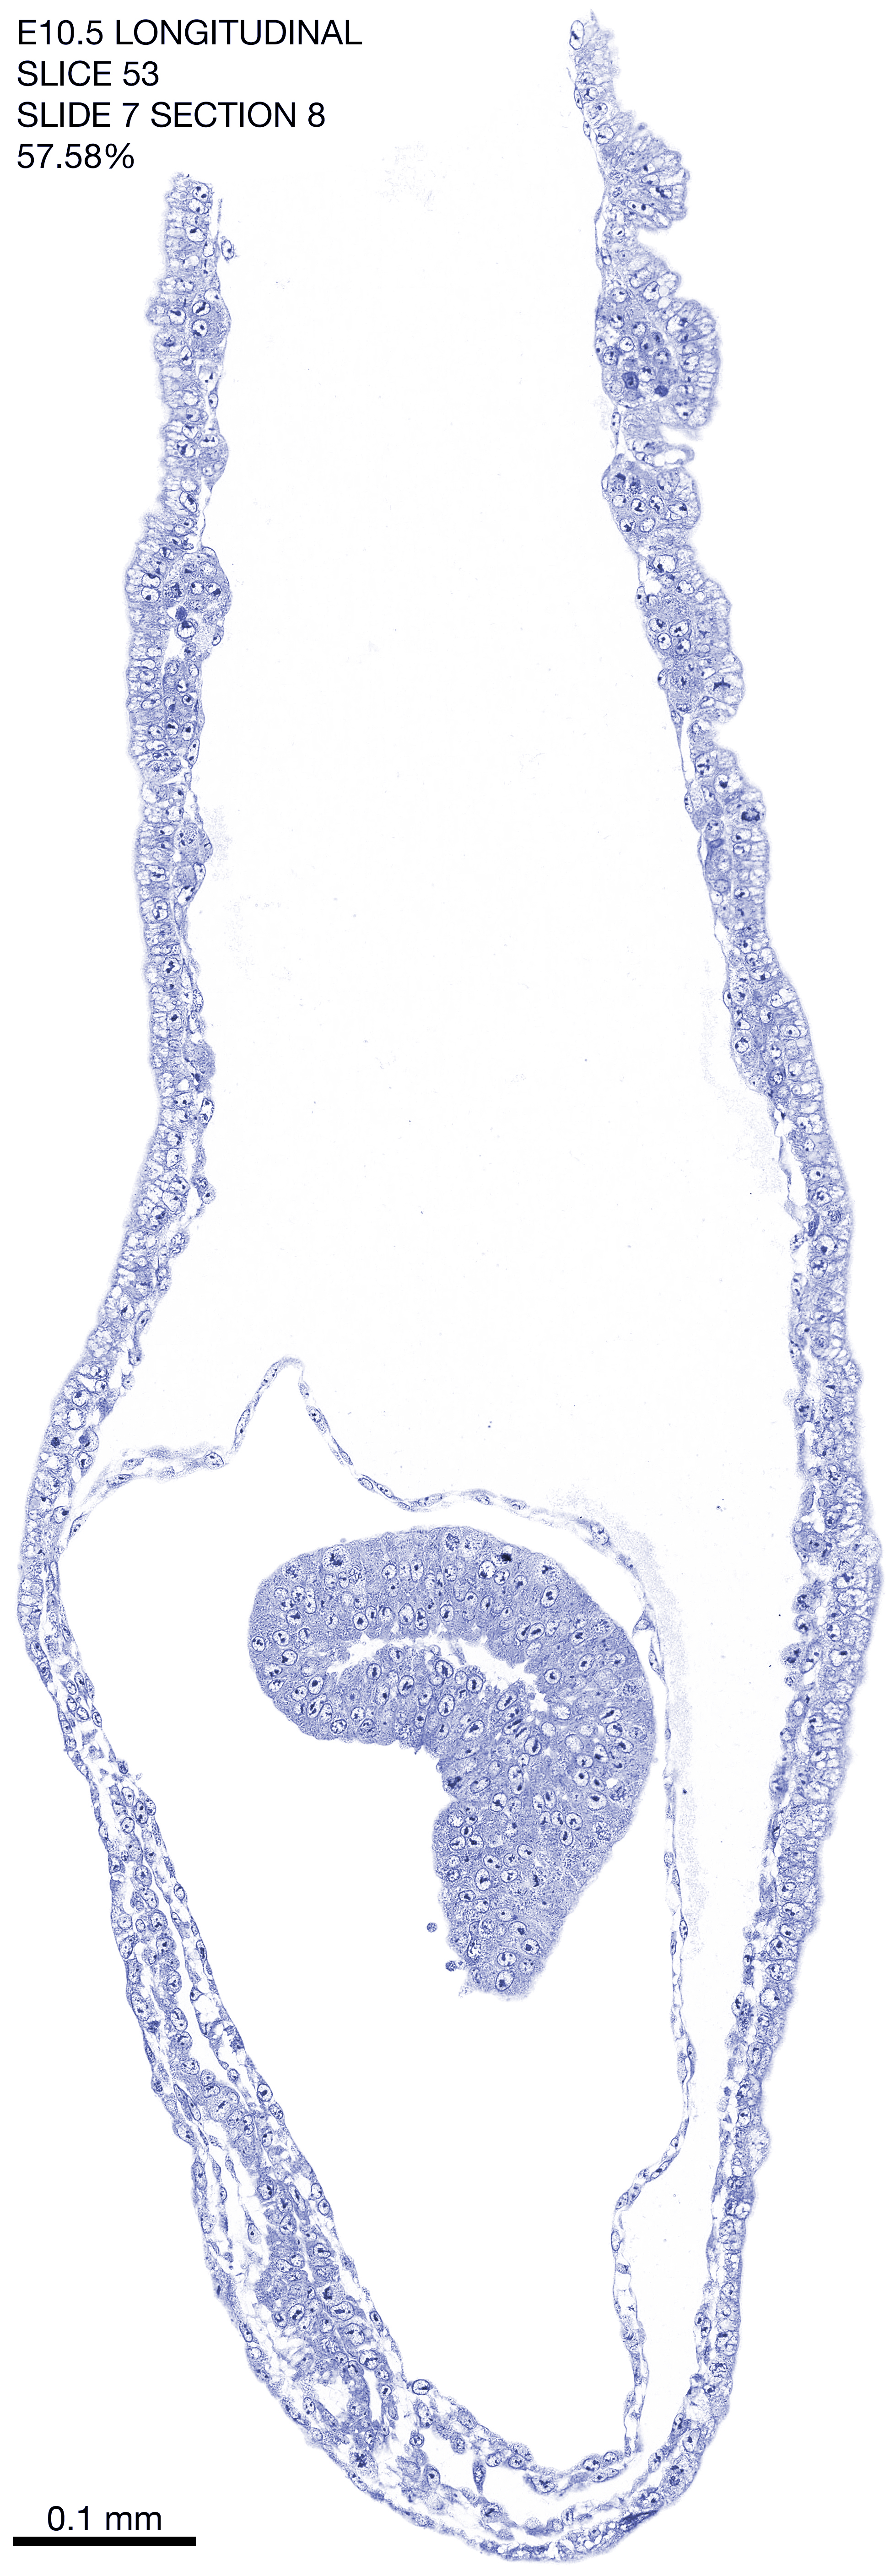

E10.5 Longitudianal Archive This page contains jpg files of ALL SLICES (each 3µm thick) that were scanned of the E10.5 longitudinally cut specimen. Download: Large | High Res Download: Large | High Res Download: Large | High Res Download: Large | High Res Download: Large | High Res Download: Large | High Res Download: Large | High Res Download: Large | High Res Download: Large | High Res Download: Large | High Res Download: Large | High Res Download: Large | High Res Download: Large | High Res Download: Large | High Res Download: Large | High Res Download: Large | High Res Download: Large | High Res Download: Large | High Res Download: Large | High Res Download: Large | High Res Download: Large | High Res Download: Large | High Res Download: Large | High Res Download: Large | High Res Download: Large | High Res Download: Large | High Res Download: Large | High Res Download: Large | High Res Download: Large | High Res Download: Large | High Res Download: Large | High Res Download: Large | High Res Download: Large | High Res Download: Large | High Res Download: Large | High Res Download: Large | High Res Download: Large | High Res Download: Large | High Res Download: Large | High Res Download: Large | High Res Download: Large | High Res Download: Large | High Res Download: Large | High Res Download: Large | High Res Download: Large | High Res Download: Large | High Res Download: Large | High Res Download: Large | High Res Download: Large | High Res Download: Large | High Res Download: Large | High Res Download: Large | High Res Download: Large | High Res Download: Large | High Res Download: Large | High Res Download: Large | High Res Download: Large | High Res Download: Large | High Res